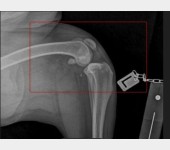

Mój ukochany Max ma dysplazje stawów tylne nogi oraz biodra odmawiają posłuszeństwa. Dotychczas starałam się finansować każdą wizytę, operację, zabiegi i rehabilitację. Niestety, nadszedł moment, gdy zostałam postawiona pod ścianą. Z osoby wspomagającej, mój przyjaciel i ja staliśmy się potrzebującymi.

Niestety stopień zwyrodnienia stawów i poziom zaawansowania choroby kwalifikuje Maxa na operację wstawienia endoprotez w obu biodrach, których koszt mimo moich oszczędności przekracza moje możliwości